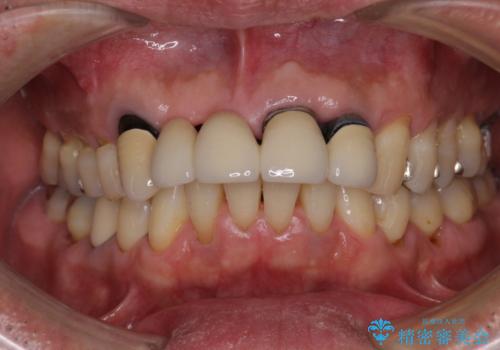

- 前歯のブリッジのせいで話しにくく、金属の縁などが露出して見栄えが悪いので、作り直したいとのことで来院された患者様です。

土台となる歯は根管治療の結果が良好ではないため、根管治療からやり直しをした後、オールセラミックブリッジにて補綴することとしました。

露出していた歯根や金属の縁が見えてしまい、人前で話すときの目線が気になっていらっしゃいましたが、歯肉の位置に縁を合わせてことで自然な仕上がりとなりました。

露出していた歯根が覆われるため、歯冠が長く見えてしまうことが懸念されましたが特に気になることはなく、患者様には大変満足していただきました。